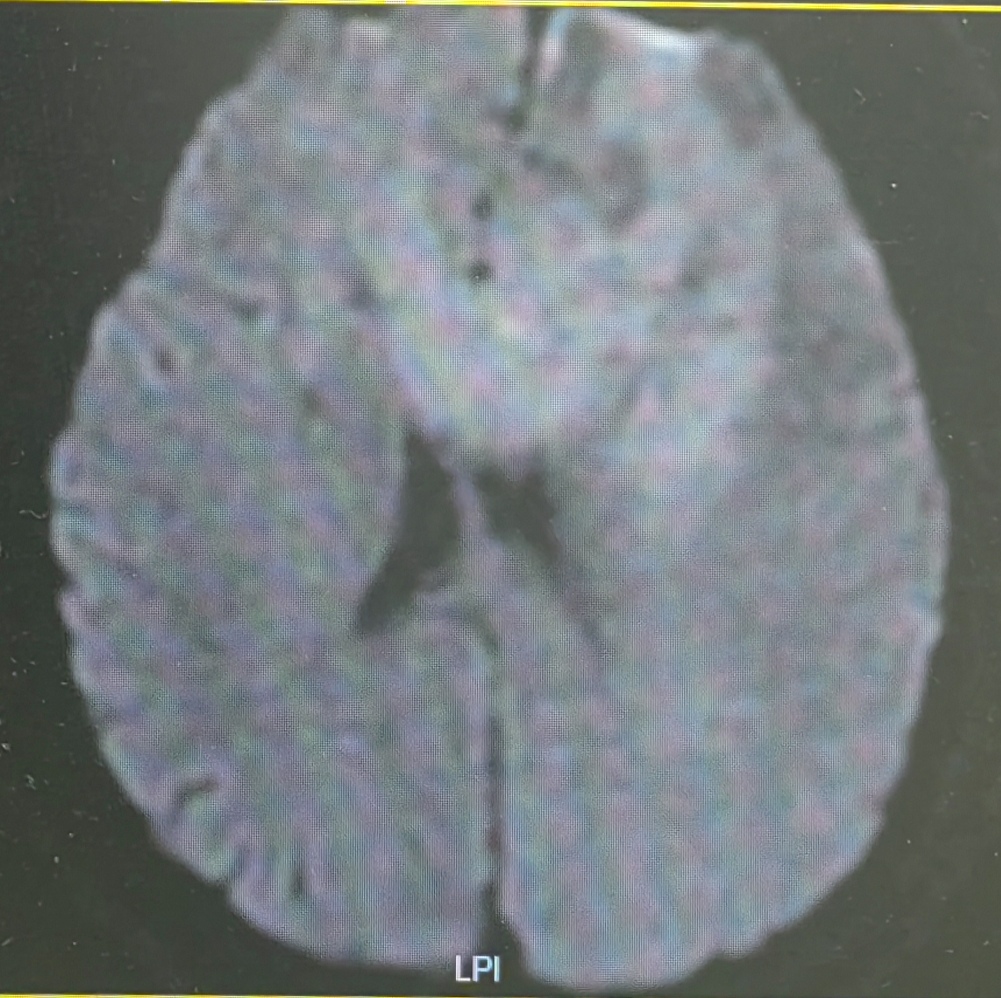

DWI呈高信号

结合病变影像学特点,怀疑中枢神经系统淋巴瘤,讨论后决定先行活检明确病理性质。完善检查,待患者停用阿司匹林一周后,局麻+镇痛镇静下行立体定向框架下取活检术。